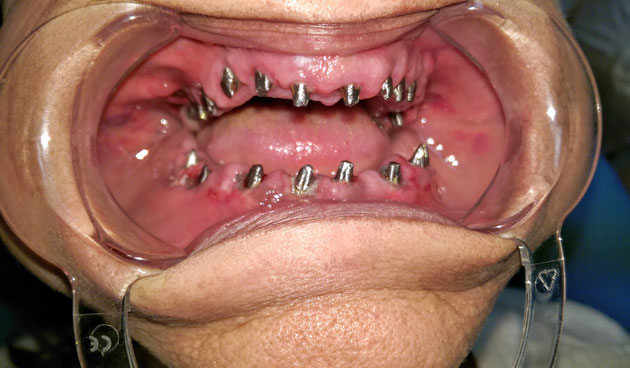

Azonnal terhelhető implantátum szájba helyezés közben

Az elmúlt fél év néhány IHDE azonnal terhelhető implantációjáról készült fotósorozatunkat ezen a linken találja.